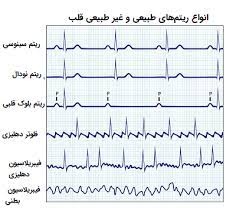

قیمت: 58٬000 تومان - دسته بندی فایل: علوم پزشکیپاورپوینت مراحل خواندن و تفسیر ECG

فروش ویژه پاورپوینت حرفه ای مراحل خواندن و تفسیر ECG با تخفیف استثنایی فقط 91634 هزار تومان تعداد اسلاید : 56 اسلاید